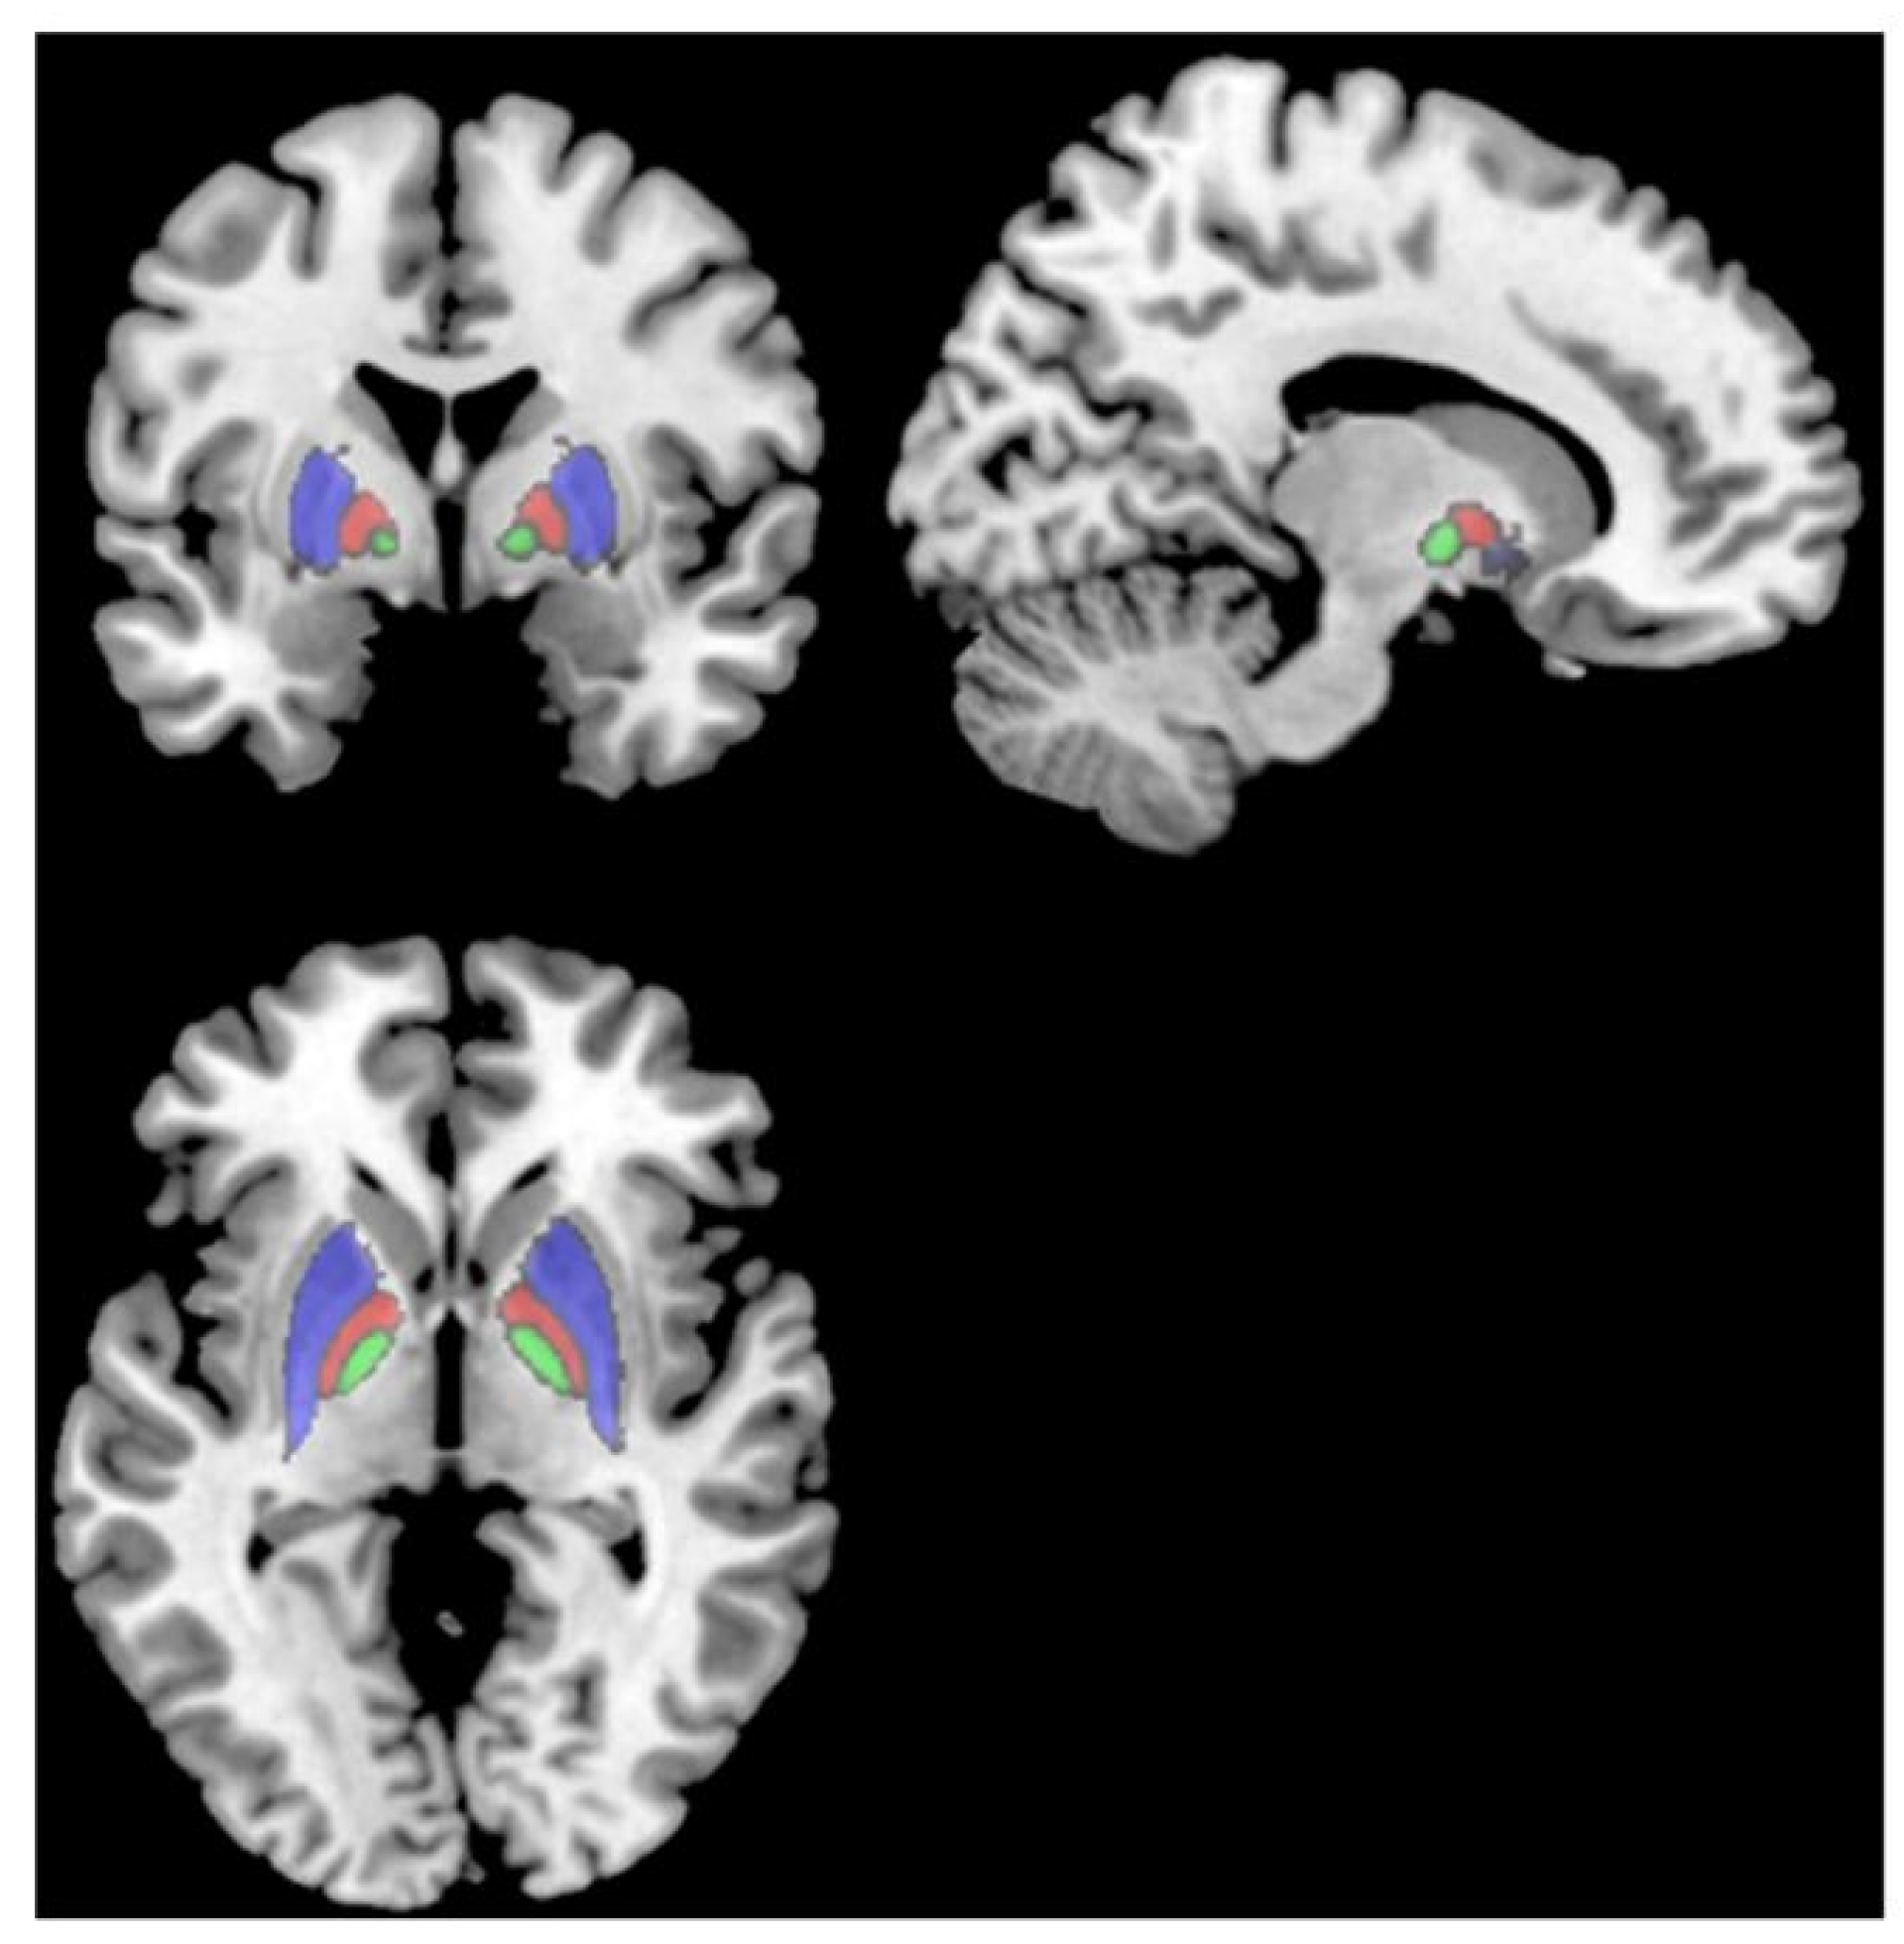

2. Basal Ganglia Dysfunction in Long-COVID Fatigue: Evidence from Neuroimaging

2.3. Mismatch in Structural Architecture

| Hafiz et al., [21] | 46 COVID-19 vs. 30 controls | 2 weeks post-discharge | Fatigue | Hospitalized | Higher gray matter volume in limbic regions and basal ganglia; correlation with fatigue |

| Heine et al., [22] | 50 long-COVID vs. 47 controls | Median 7.5 months | Anxiety, depression, sleep problems in long-COVID | 13% Hospitalized | Thalamus and basal ganglia volume loss, surface deformations, altered diffusion; correlated with fatigue |

| Deters et al., [23] | 33 mild COVID-19 patients | <6 months (n = 18) vs. >6 months (n = 15) | Persistent fatigue in some >6 month patients | Not hospitalized | Smaller putamen, pallidum, thalamus volumes in >6 month group, especially fatigued; frontal hypometabolism |

| Luo et al., [17] | 32 post-COVID-19 patients (16 fatigued, 16 non-fatigued) | 6.9 ± 4.8 months (FT), 8.5 ± 5.7 months (NF) | Not specified | Not hospitalized | Decreased globus pallidus activity in both fatigued and non-fatigued groups compared to healthy controls; non-fatigued group showed greater hypometabolism; right hemisphere more affected in both groups |